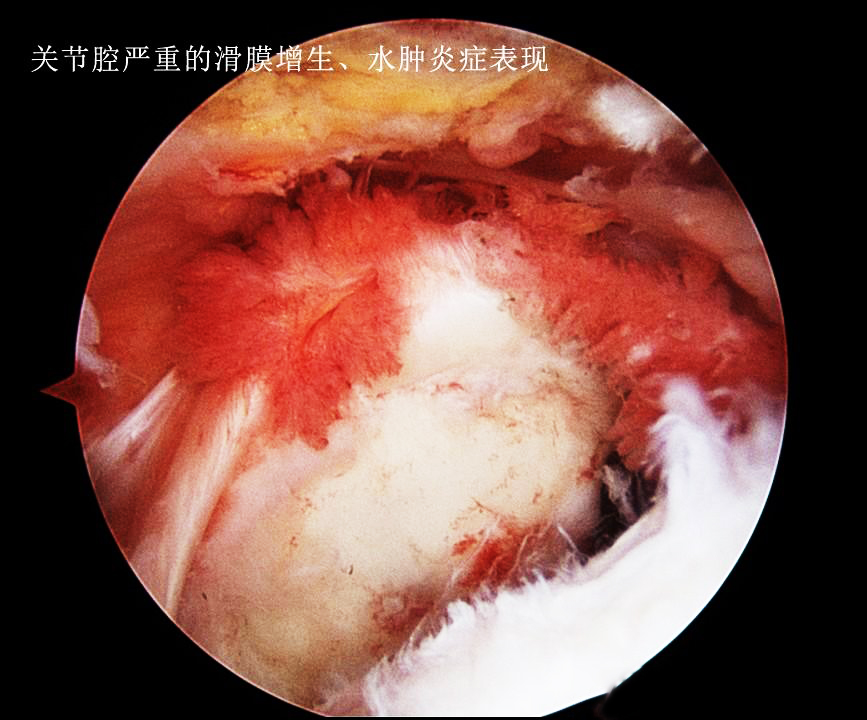

简单的说,无论是骨性关节炎还是痛风性关节炎,甚至半月板的损伤等导致关节积液的原因,主要是由于各种疾病的病理改变会刺激到关节内的一个重要结构,就是滑膜。滑膜一旦被刺激到就会产生无菌性的炎症,从而导致渗出,这就是关节积液的由来,类似于眼睛里进了沙子就会流眼泪。翻遍手机也没有找到膝关节内滑膜炎的照片,可能是被无意当中删掉了,但是大家可以用肩关节的滑膜炎的照片理解一下滑膜炎症到底是什么样子的。

大家可以看看发炎的滑膜是这个样子的,它的表面是布满了新生血管的。这张照片还不是比较重的,严重的膝关节内滑膜炎会导致整个关节腔内都布满这种肿胀增生的滑膜组织。谢医生第一次做关节镜看见这种严重增生伴有无菌性炎症滑膜的时候,印象是一种海洋的生物---海葵。

看起来这些病态的滑膜就像是魔鬼的触角一样恐怖,事实也是如此,尤其是对于类风湿关节炎以及痛风性关节炎的患者,这些滑膜会在关节内长久的存在,不断侵蚀关节的软骨以及骨骼。下图就是一例严重类风湿关节炎患者的核磁片子,他的关节软骨以及骨骼看起来已经像是被老鼠啃噬过一样了,这都归咎于类风湿滑膜炎的侵犯!

那种鲜艳的红色,并不是滑膜本身的颜色,而是由于无菌性炎症导致滑膜内出现了大量的新生的血管。相信所有人都明白热胀冷缩的道理,血管也是一样的,当血管受热以后,血管的细胞会变得扩张,如果本身就是由于滑膜的炎症,导致了血管渗出出现了积液,您继续用长时间热敷的办法去刺激有炎症的滑膜,那么是不是会导致滑膜炎症渗出的加重呢?